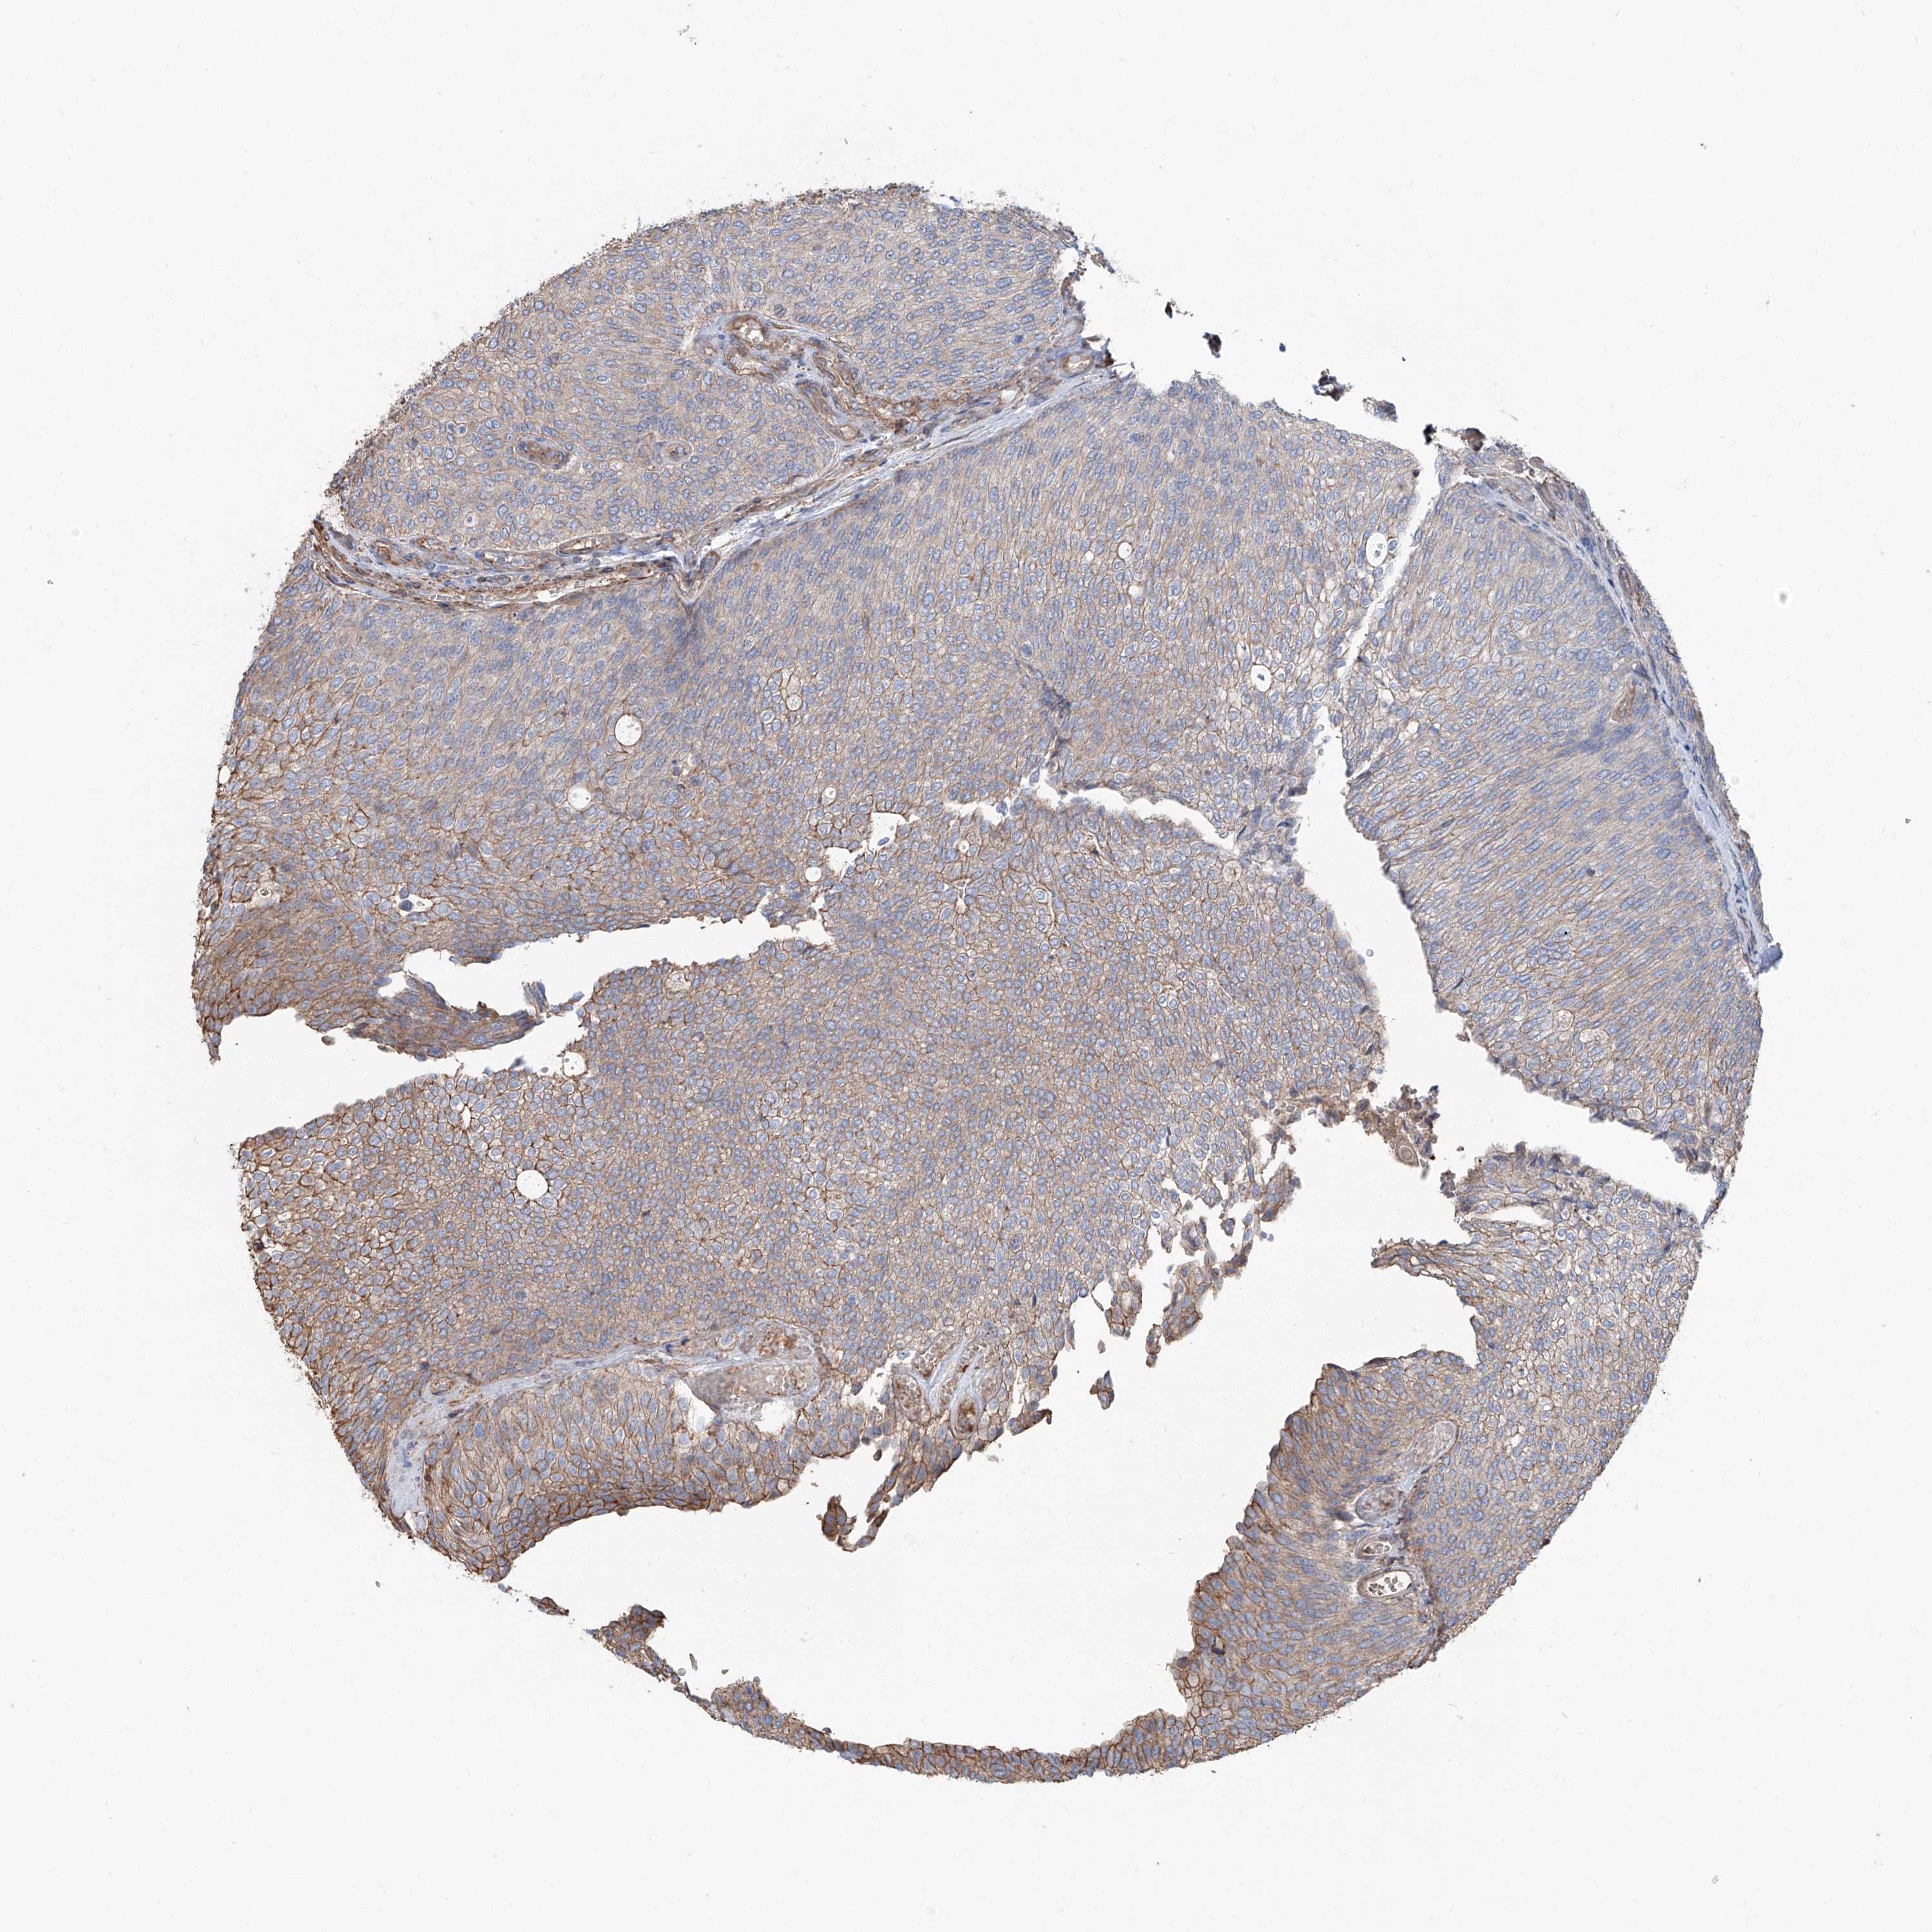

UROTHELIAL CANCER - Protein expressioni

A mouse-over function shows sample information and annotation data. Click on an image to view it in a full screen mode. Samples can be filtered based on level of antibody staining by selecting one or several of the following categories: high, medium, low and not detected. The assay and annotation is described here.

Note that samples used for immunohistochemistry by the Human Protein Atlas do not correspond to samples in the TCGA dataset.

Antibody stainingi

Antibody staining in the annotated cell types in the current human tissue is reported as not detected, low, medium, or high, based on conventional immunohistochemistry profiling in selected tissues. This score is based on the combination of the staining intensity and fraction of stained cells.

Each image is clickable and will lead to virtual microscopy that enables deeper exploration of all samples and also displays staining intensity scores, fraction scores and subcellular localization as well as patient and tissue information for each sample.

Antibody HPA015986

Antibody HPA031974

Antibody HPA040616

Urothelial carcinoma, Low grade

Urothelial carcinoma, High grade